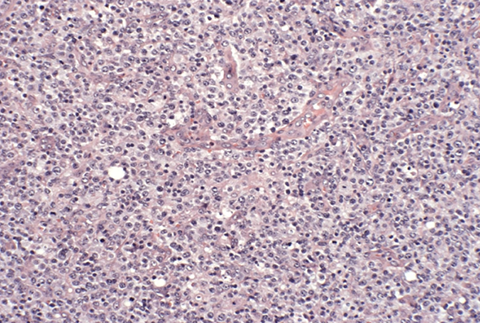

Angioimmunoblastic T-cell lymphoma and other nodal lymphomas of T follicular helper (TFH) cell origin

- Angioimmunoblastic T-cell lymphoma